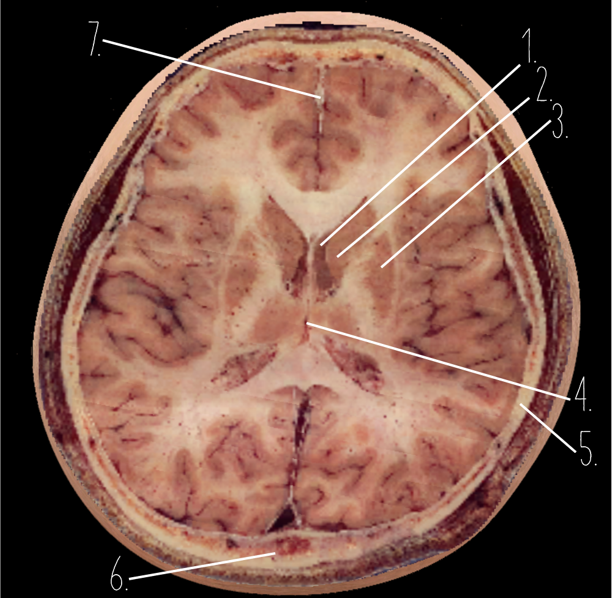

1?

Choroid Plexus

2?

Lateral Ventricle

3?

Caudate Nucleus

4?

Third Ventricle

5?

Parietal Bone

6?

Occipital Bone

7?

Falx Cerebri

1?

Anterior Horn of the Lateral Ventricle

2?

Putamen

3?

Thalamus

4?

Internal Occipital Protuberance

5?

Cerebellar Vermis

6?

Third Ventricle